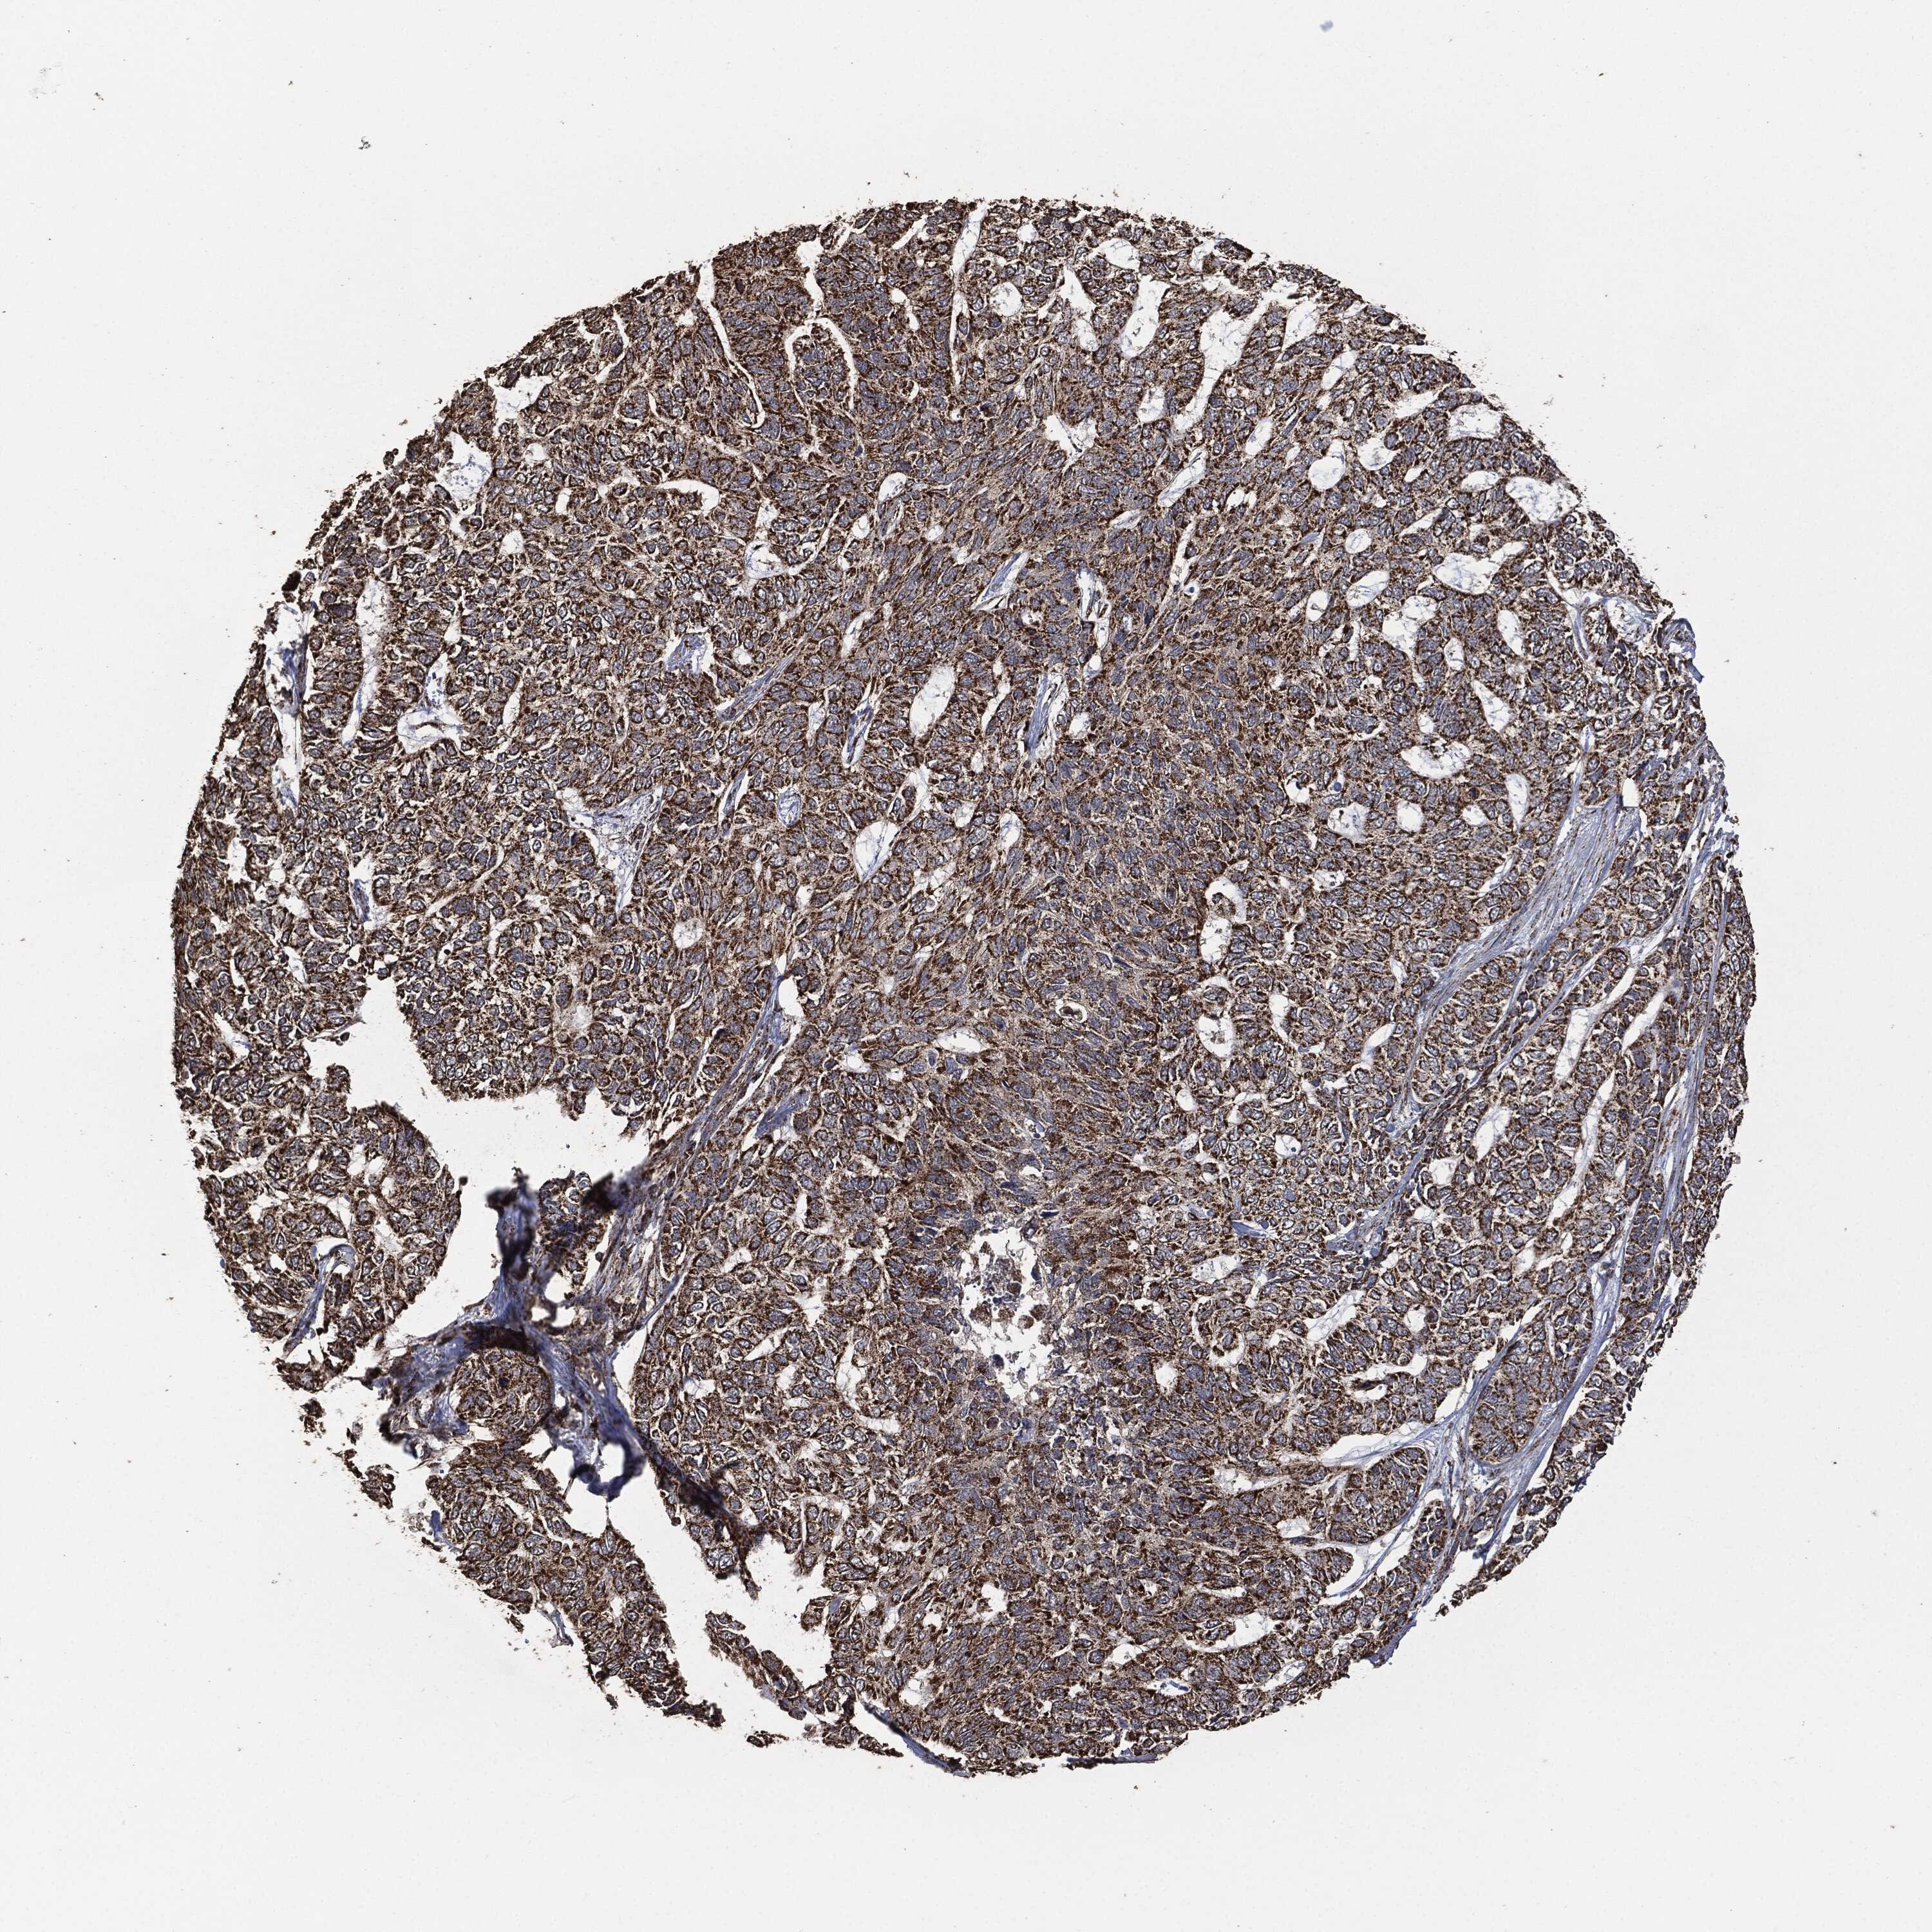

SKIN CANCER - Protein expressioni

A mouse-over function shows sample information and annotation data. Click on an image to view it in a full screen mode. Samples can be filtered based on level of antibody staining by selecting one or several of the following categories: high, medium, low and not detected. The assay and annotation is described here.

Antibody stainingi

Antibody staining in the annotated cell types in the current human tissue is reported as not detected, low, medium, or high, based on conventional immunohistochemistry profiling in selected tissues. This score is based on the combination of the staining intensity and fraction of stained cells.

Each image is clickable and will lead to virtual microscopy that enables deeper exploration of all samples and also displays staining intensity scores, fraction scores and subcellular localization as well as patient and tissue information for each sample.

Antibody HPA006723

Antibody CAB080348

Staining

High

Medium

Low

Not detected

Intensity

Strong

Moderate

Weak

Negative

Quantity

>75%

75%-25%

<25%

None

Location

Nuclear

Cytoplasmic/membranous

Cytoplasmic/membranous,nuclear

Squamous cell carcinoma, NOS

Squamous cell carcinoma, metastatic, NOS

Basal cell carcinoma

Papilloma, NOS